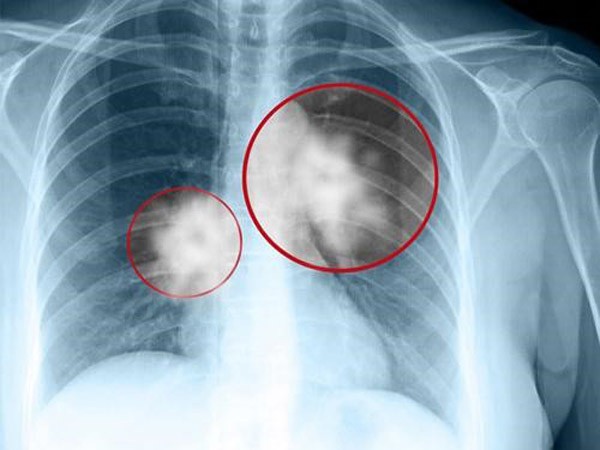

Từ h́nh ảnh X-quang, bác sĩ nói phổi của cô có màu trắng lớn, đó là viêm bạch huyết ung thư, có nghĩa là ung thư phổi di căn. Thật đáng tiếc khi không c̣n thời gian để phẫu thuật và hóa trị. Chỉ trong 5 ngày, hơi thở của Tiểu Mơ ngày càng yếu đi và qua đời